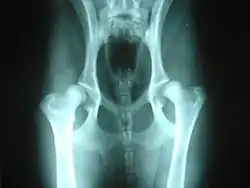

A number of conditions in dogs may be aggravated by or may show slow or no improvement as a result of weight bearing exercise. Among these are hip dysplasia and osteochondritis dissecans (OCD), conditions most common in medium to large purebred dogs, such as German Shepherds, Labrador Retrievers or Golden Retrievers; chronic degenerative radiculomyelopathy (CDRM), a degenerative disease of the spinal cord which causes hind limb problems in German Shepherds; and luxating patella which is seen predominantly in small and toy breeds.[2]